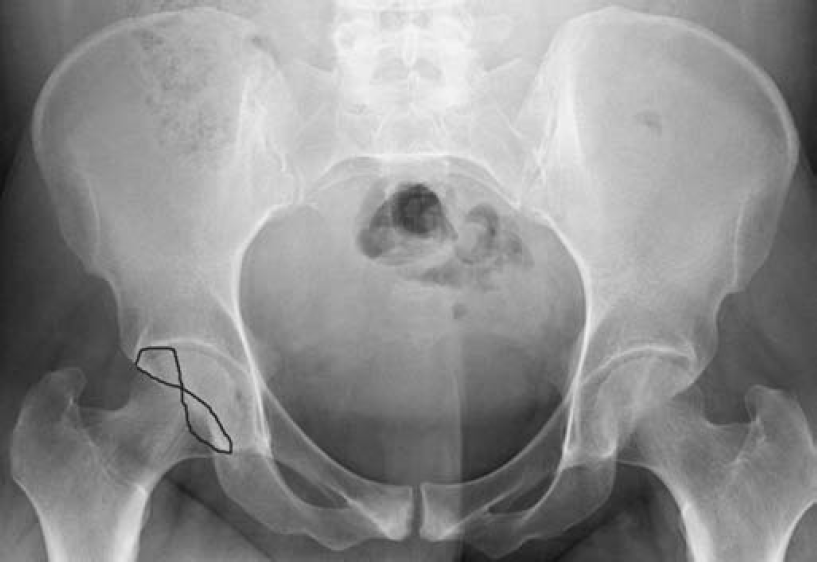

髓关节撞击综合征(femoroacetabular-impingement,FAI)是引起髋关节疼痛及髋关节进行性退行性变的一种常见病因。一般采用骨盆X线前后位照片筛查。骨盆照片时X线中心线应对准尾骨中心及耻骨联合,以保证骨盆不旋转。FAI主要分为3种类型:凸轮型、钳型和混合型。混合型FAI同时具有凸轮型和钳型的异常。凸轮型是股骨头颈连接处形成/发育异常所致,表现为股骨头颈连接处骨性隆起或“枪柄样”改变(缺乏正常的凹度)(图1)。钳型FAI表现为髋臼覆盖或位置异常,可根据在X线平片上见到深髋臼、髋臼前突或髋臼后倾的表现而诊断。深髋臼及髋臼前突X线表现为股骨头及髋臼相对髂骨坐骨线位置异常(图2)。髋臼后倾表现为交叉征、髋臼后壁征、坐骨棘突出征(图3)。

图3 25岁女性,双髋关节疼痛

骨盆前后位片显示双髋关节交叉征,这是髋臼后倾的一个征象。髋臼后倾可能是FAI引起髋关节疼痛的一个原因。为了更好地显示病变,图中用线条勾画了右侧髋臼交叉征